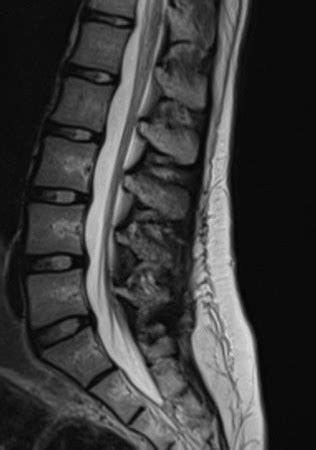

Alright, let’s get down to business and talk about what doctors are actually looking for when they examine a transverse myelitis MRI . The primary goal is to spot inflammation or swelling within the spinal cord. In a healthy spinal cord, the MRI typically shows a uniform, gray appearance. However, when transverse myelitis is present, there are specific signs that pop up. The most common finding is an abnormal signal intensity within the spinal cord on what are called T2-weighted images. Basically, areas of inflammation and swelling tend to appear brighter or ‘hyperintense’ on these images compared to the normal spinal cord tissue. This brightness is indicative of increased water content in the inflamed area. Doctors will also look for the lesion , which is the specific area of damage. This lesion is often described as a linear or patchy area of increased signal intensity. The length and location of this lesion are super important. Transverse myelitis typically affects a specific segment or segments of the spinal cord, meaning the inflammation is usually confined to one or a few contiguous levels. The lesion might span one to three vertebral segments. The radiologists will meticulously measure its size and note its exact position – for instance, whether it’s in the cervical (neck), thoracic (mid-back), or lumbar (lower back) region of the spine. Furthermore, they’ll observe if the inflammation affects the entire cross-section of the spinal cord (which is characteristic of transverse myelitis) or just a portion. Another crucial observation is whether the inflammation extends over multiple segments or is isolated. In some cases, especially if contrast dye is used, the lesion might enhance , meaning it lights up brightly after the contrast is administered. This enhancement pattern can provide further clues about the nature of the inflammation. It’s important to remember that an MRI can also help rule out other conditions that mimic transverse myelitis, such as spinal cord compression from a tumor or herniated disc, bleeding, or other demyelinating diseases like multiple sclerosis. So, the transverse myelitis MRI is not just about finding the inflammation; it’s about painting a comprehensive picture of what’s happening in the spinal cord.